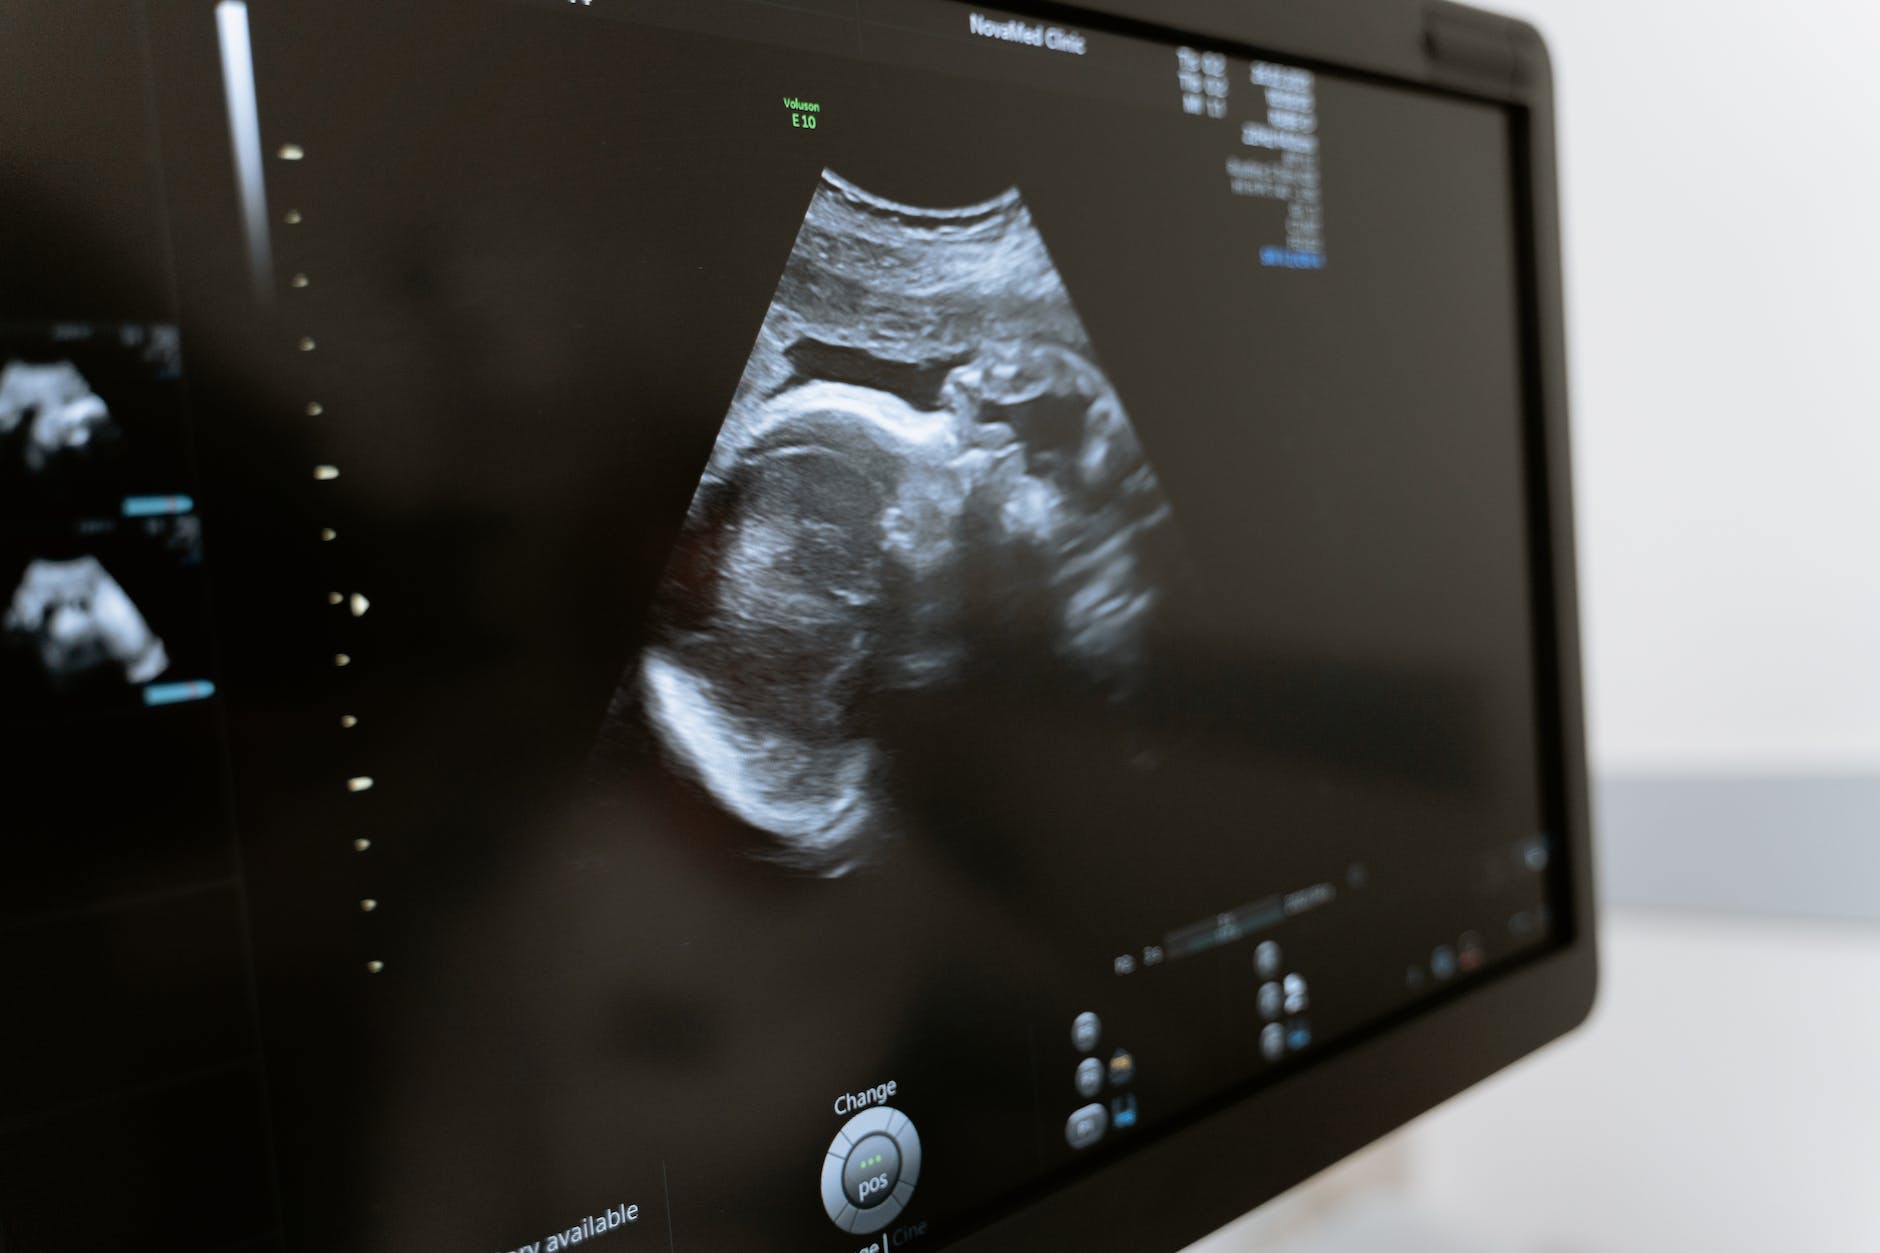

When I was a medical student, I really really enjoyed my obstetrics rotation. For the whole time I was there, I felt quite strongly that obstetrics was what I wanted to specialise in, “when I grew up”. I loved going to clinic, measuring baby bumps, learning about the complicated and fascinating world of pregnancy. I was amazed the strength of the human body. We had to be present at and support a specific number of deliveries, to get signed of for that rotation. I think my first delivery was at Harold Wood Hospital (it no longer exists). My 22-year old self, was just gobsmacked.

I wonder what my life would have been like if I made a different choice at the end of my house officer year in 2001 to apply for an obstetric and gyanecology rotation/senior house officer post. By now, if I had continued I would be an obstetric consultant with two decades of experience under my belt. I would like to think, that despite the horror show that is the NHS right now, I would enjoy the practice of obstetric medicine. I imagine, some parts are rewarding, if there is a good team and resources available. I am sure there was a time when obstetricians knew their patients there was much more continuity of care. Therefore following a woman’s journey through her pregnancy and beyond would have been rewarding and reassuring for both sides.